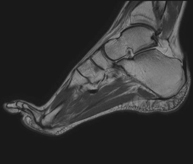

- Ankle MRI

Examination to study the joint and its frequent ligament injuries (sprains) as well as damage to other structures such as cartilage or bone. It is also very useful for diagnosing disorders of the Achilles tendon (tendinitis, ruptures). Duration: approximately 20 minutes. It is a radiation-free procedure.

- Foot MRI

Examination for the study of injuries to tendons, muscles and small joints. Allows for effective assessment of cartilage injuries. It is also very useful for completing the preliminary ultrasound examination. It is a radiation-free procedure. It lasts approximately 20 minutes.